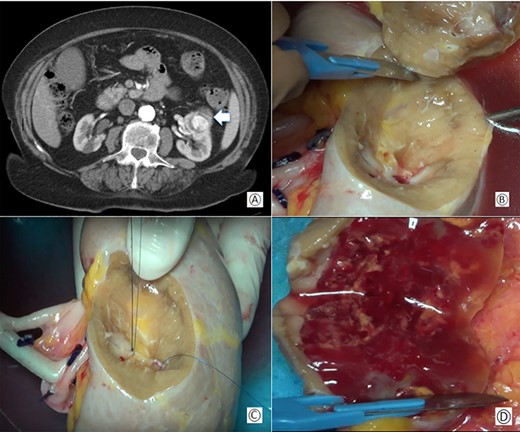

CT-scan showed a mass of 50 × 30 × 40 mm diameter in the anterior and middle region of the left kidney involving the medium calyceal group (Fig. 1A). Due to the size of the tumor and its central location, an ex-vivo PN and kidney autotransplantation was planned.

(A) Preoperative computed tomography: the white arrow shows the renal mass; (B) removal of the tumor during bench surgery; (C) suture of the renal calices during bench surgery; (D) macroscopic examination of the surgical piece.

The renal capsule was incised and the tumor was resected with at least 1 cm margin of healthy parenchyma, with microscopic frozen section examination negative for neoplastic residue (Fig 1B–D). The sectioned vessels were tied with polypropylene 6–0 (Ethicon®), while the renal calices and the pelvis were sutured with a polypropylene 7–0 running suture (Ethicon®) (Fig. 2A and B). The kidney was repositioned in its natural location (Fig. 2C). End-to-end artery anastomosis with polypropylene 7–0 separate stitches and end-to-end vein anastomosis with two running sutures in polypropylene 6–0 were performed. Double J silicone catheter (Coloplast, Bologna) was inserted and the ureteral stumps were anastomosed with PDS 6–0 (Ethicon®). The hemostasis on the residual renal parenchyma was completed with polypropylene 6–0 separate stitches and with a hemostatic sponge (TachoSil®- Nycomed, Konstanz, Germany). Two drains were placed anteriorly and posteriorly to the surgical site.